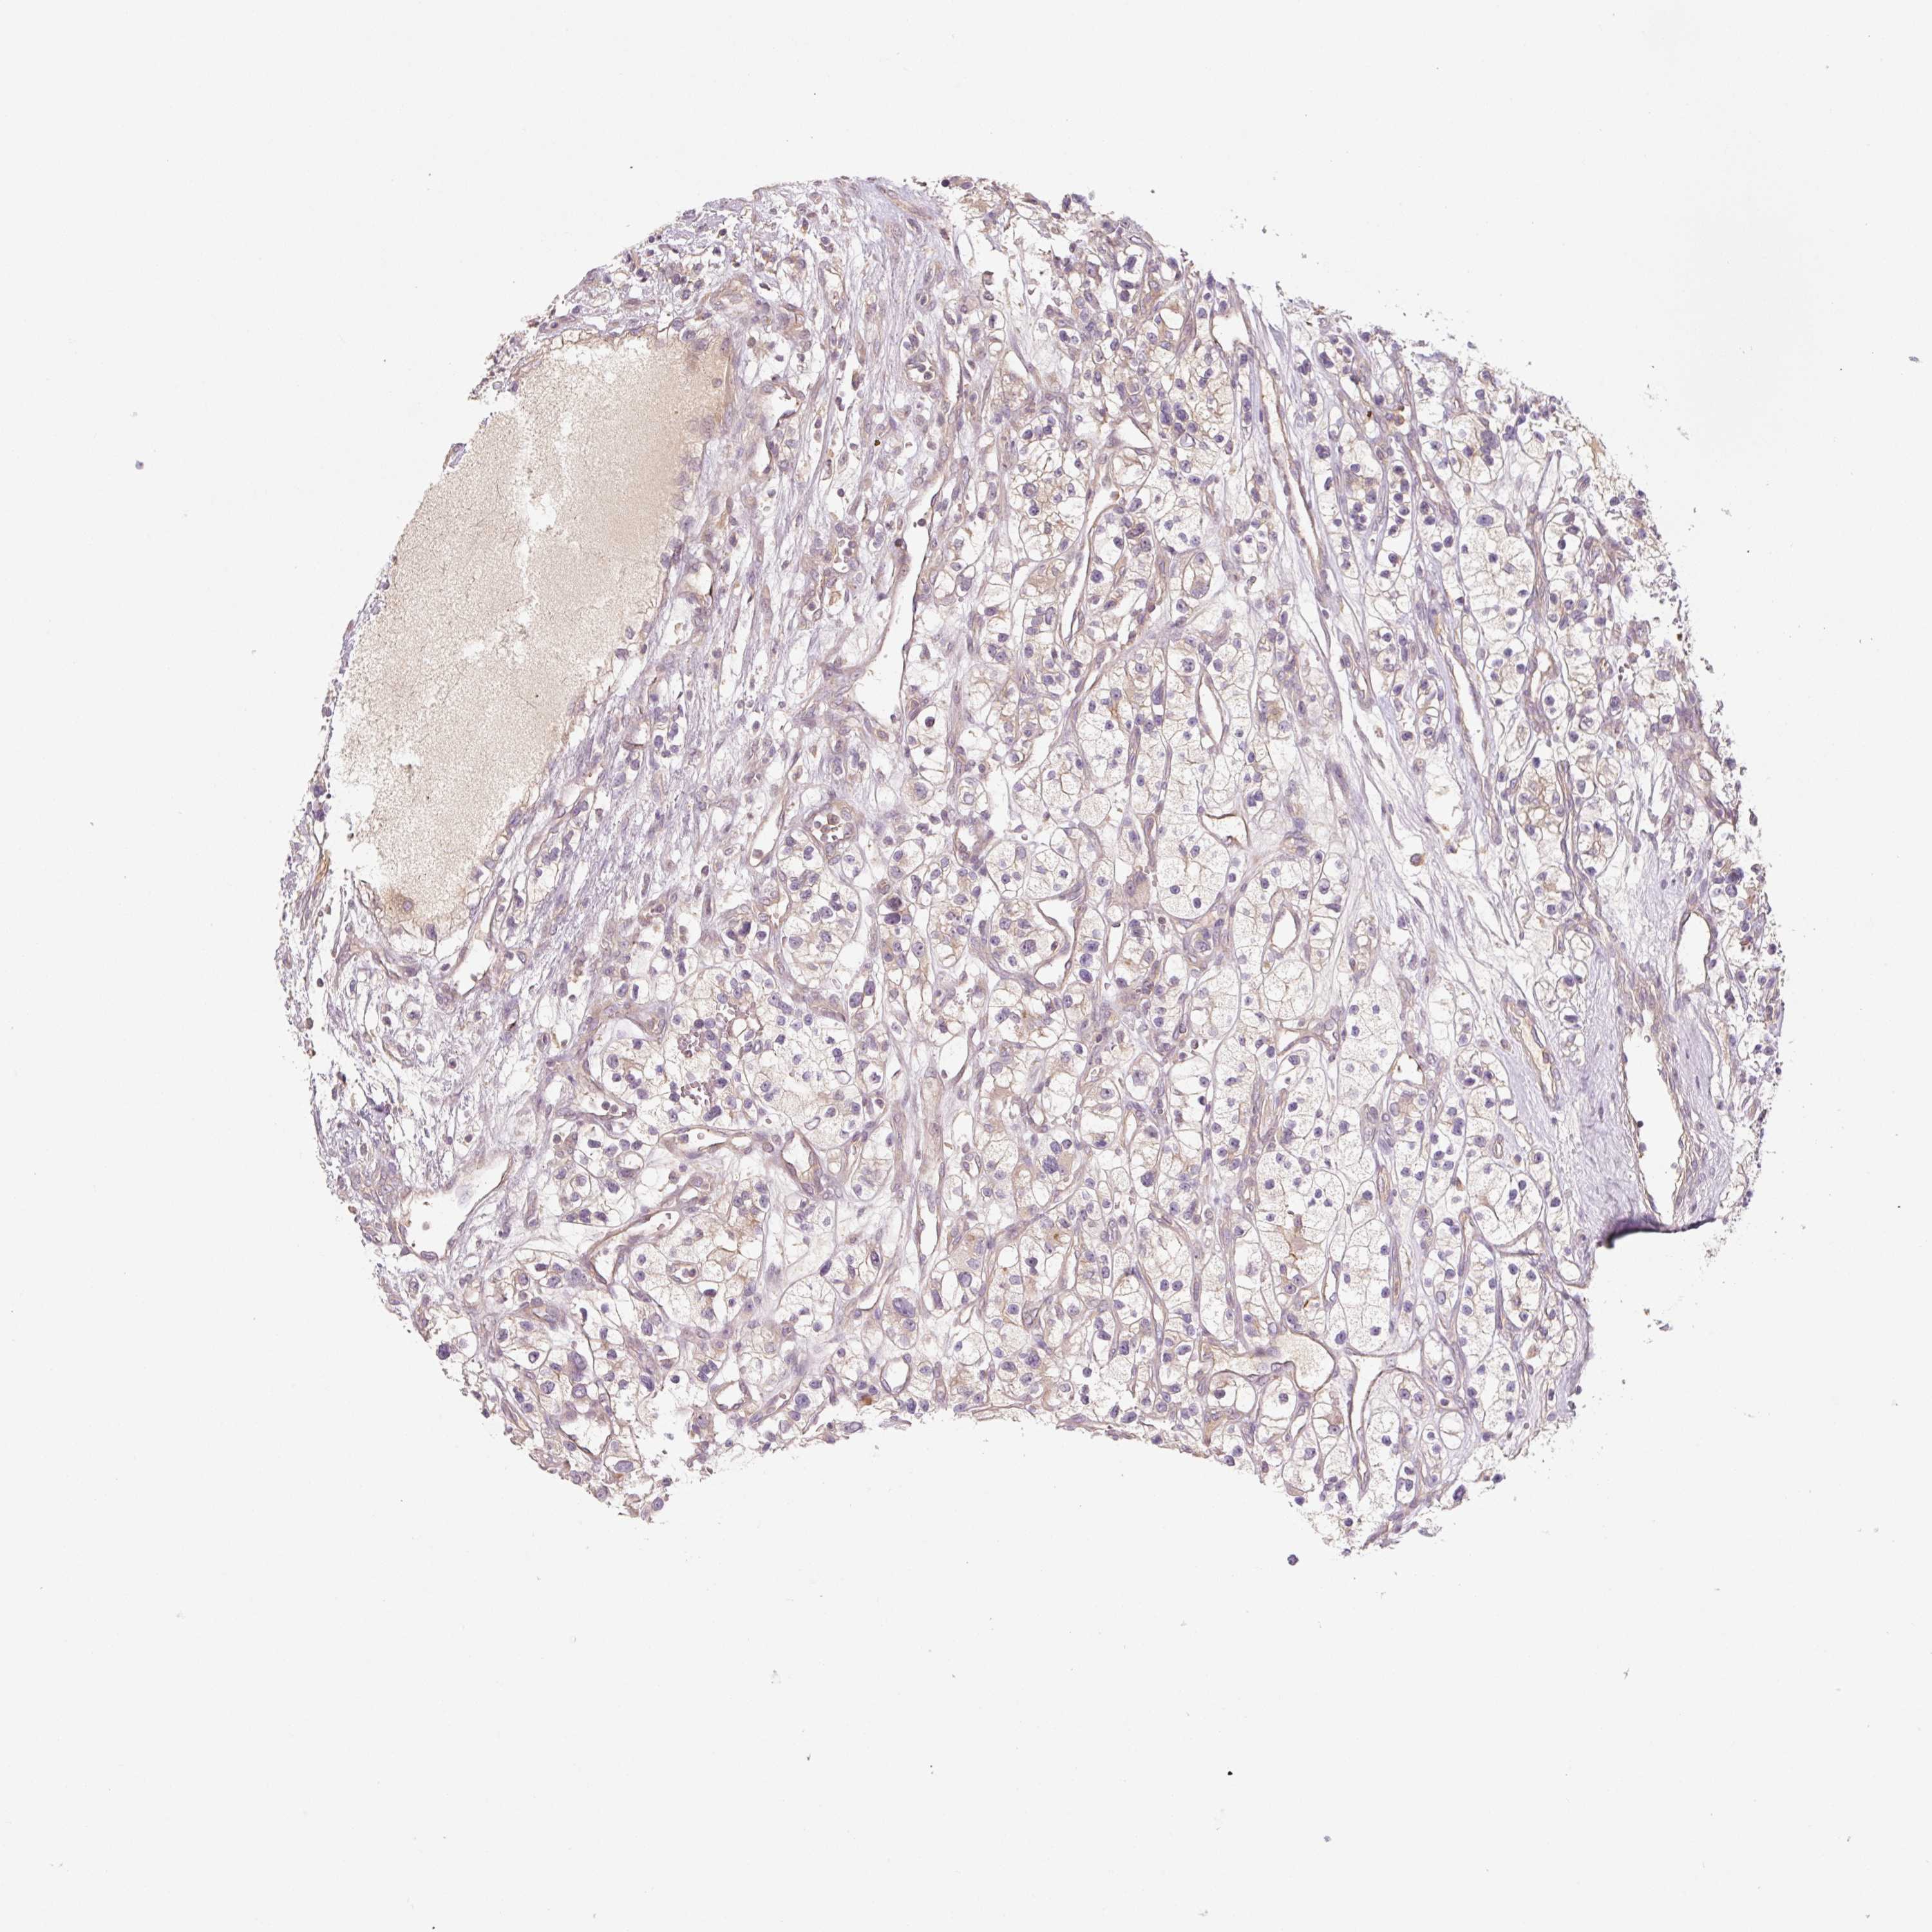

KIDNEY RENAL CLEAR CELL CARCINOMA (VALIDATION) - Interactive survival scatter ploti

The Survival Scatter plot shows the clinical status (i.e. dead or alive) for all individuals in the patient cohort, based on the same data that underlies the corresponding Kaplan-Meier plots. Patients that are alive at last time for follow-up are shown in blue and patients who have died during the study are shown in red.

The x-axis shows the expression levels (FPKM) of the investigated gene in the tumor tissue at the time of diagnosis. The y-axis shows the follow-up time after diagnosis (years). Both axes are complimented with kernel density curves demonstrating the data density over the axes. The top density plot shows the expression levels (FPKM) distribution among dead (red) and alive patients (blue). The right density plot shows the data density of the survived years of dead patients with high and low expression levels respectively, stratified using the cutoff indicated by the vertical dashed line through the Survival Scatter plot. This cutoff is automatically defined based on the FPKM cutoff that minimizes the p-score. The cutoff can be changed by dragging the vertical line or by entering a cutoff value in the square labeled "Current cut-off".

Under the Survival Scatter plot the p-score landscape (black curve; left axis) is shown together with dead median separation (red curve; right axis). Dead median separation is the difference in median mRNA expression between patients who have died with high and low expression, respectively. It is calculated as follows: median FPKM expression of dead patients with high expression - median FPKM expression of dead patients with low expression. This is intended to aid the user in visually exploring custom cutoffs and the associated p-scores and dead median separation.

Individual patient data is displayed and can be filtered by clicking on one or more of the category buttons on the top of the page. Categories describing expression level and patient information include: high, low, alive, dead, female, male and tumor stages. The scale of the x-axis can be toggled between linear and log-scale by clicking on the "x log" button. Mouse-over function shows TCGA ID, patient information and mRNA expression (FPKM) for each patient.

& Survival analysisi

Kaplan-Meier plots summarize results from analysis of correlation between mRNA expression level and patient survival. Patients were divided based on level of expression into one of the two groups "low" (under cut off) or "high" (over cut off). X-axis shows time for survival (years) and y-axis shows the probability of survival, where 1.0 corresponds to 100 percent.

C2orf73 is not prognostic in Kidney Renal Clear Cell Carcinoma (validation)

TCGA RNA samplesi

RNA-seq data is reported as average FPKM (number Fragments Per Kilobase of exon per Million reads), generated by the The Cancer Genome Atlas (TCGA) .

Normal distribution across the dataset is visualized with box plots, shown as median and 25th and 75th percentiles. Points are displayed as outliers if they are above or below 1.5 times the interquartile range. FPKM values of the individual samples are presented next to the box plot.

Average pTPM 0.6

Number of samples 100